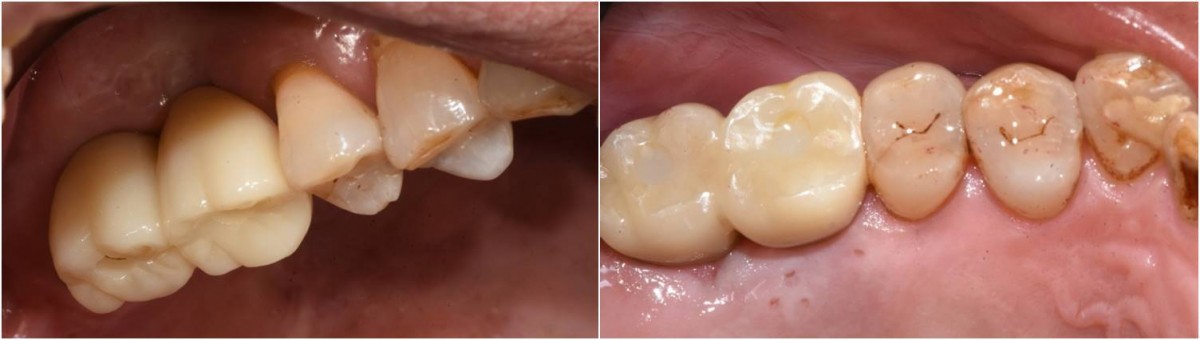

Maxillary Sinus Graft, 2 Implants, Crown Contouring

<GCaks> A 56-year-old male patient had pain-inducing caries, and perio-involved tooth mobility resulted in a tooth fracture at 1st molar. And it was removed months ago. He was a heavy smoker and showed poor oral hygiene.